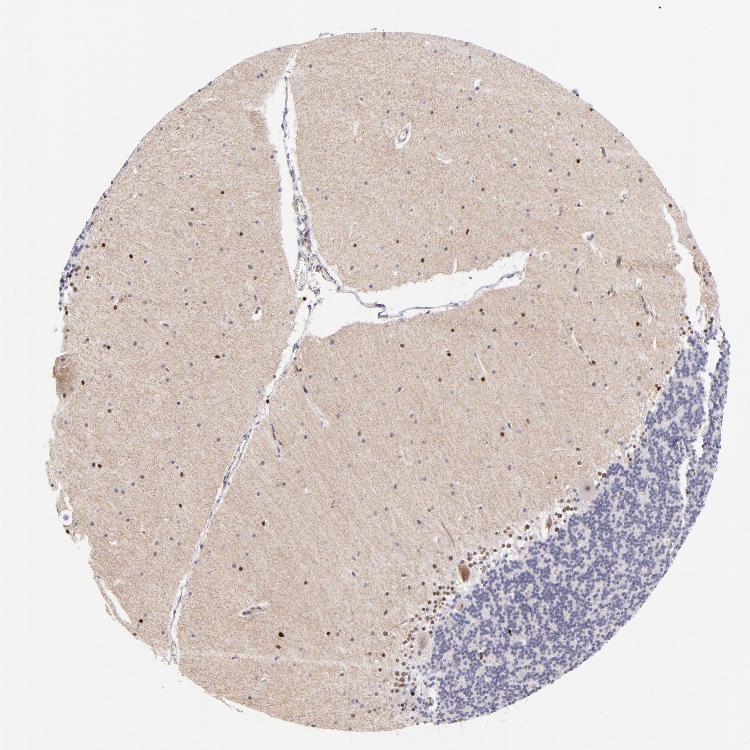

CEREBELLUM - Antibody stainingi

Antibody staining in the annotated cell types in the current human tissue is reported as not detected, low, medium, or high, based on conventional immunohistochemistry profiling in selected tissues. This score is based on the combination of the staining intensity and fraction of stained cells.

Each image is clickable and will lead to virtual microscopy that enables deeper exploration of all samples and also displays staining intensity scores, fraction scores and subcellular localization as well as patient and tissue information for each sample.

Antibody HPA001923Antibody HPA003908

Purkinje cells MediumNot detected

Cells in granular layer MediumLow

Cells in molecular layer MediumLow